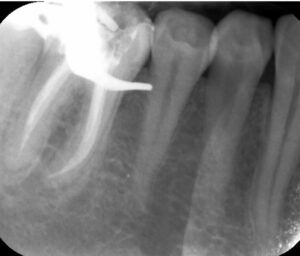

- Diagnostyka – RTG lub tomografia CBCT pozwala ocenić liczbę kanałów i obecność zmian zapalnych.

- Wypełnienie – szczelne zamknięcie kanałów gutaperką, aby uniemożliwić przenikanie bakterii.

- Systemy gorącej gutaperki – szczelne wypełnienie bez pustych przestrzeni.

- Radiografia cyfrowa – redukcja dawki promieniowania nawet o 90%.